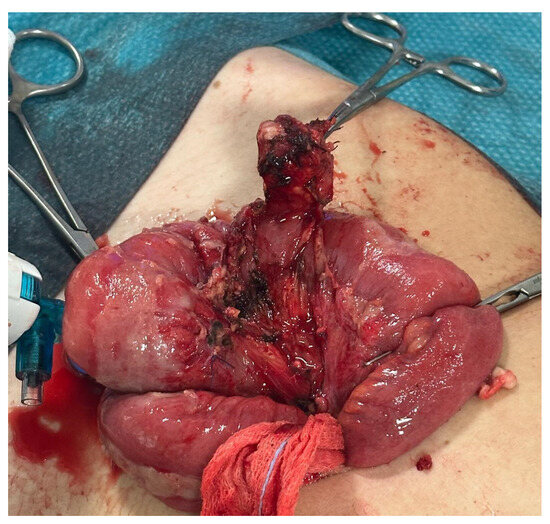

Figure 6.

Case 3—Exteriorization of MMD through umbilical access.